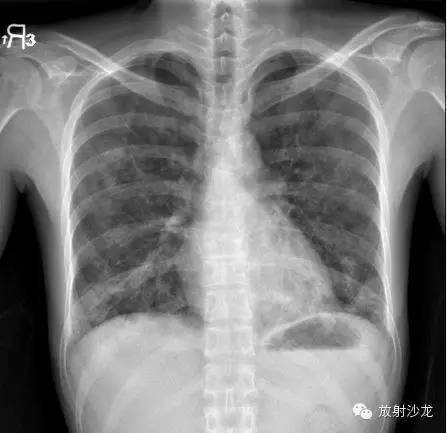

两周后的CT和X线:

胸片示两肺中下野边界不清的磨玻璃样阴影(GGO)。CT示两肺地图样分布的GGO,主要位于两肺上叶、右肺中叶及两肺下叶,其中两肺下叶多发的GGO融合并伴有小叶间隔增厚。2周后随访胸片示双肺野弥漫分布的GGO增多。患者第一次就诊时未告知自己的性取向。只告知了曾接触过染发剂。患者按肺间质性疾病给予激素治疗。然而,治疗后患者的症状和影像学表现均加重。患者血液检测结果显示艾滋病病毒阳性。支气管肺泡灌洗液GMS染色示大量的卡氏肺孢子虫。